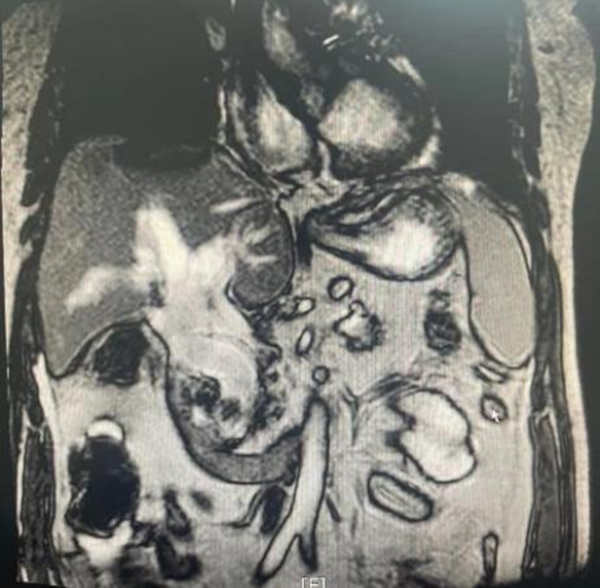

干四(普外四病区)收住一名70岁老年男性梗阻性黄疸患者,患者入院前已经反复高烧两周,多年前做过开腹胆囊切除,胆总管探查手术。肝功显示重度黄疸,合并急性肾功能不全,少尿,肌酐最高达700umol/L。患者年龄大,肝肾功差,如果采取开腹手术系二次胆道手术,难度和风险都很大。入院后虽然第一时间在彩超引导下放置了经皮经肝胆管引流,但引流液过于浓稠,退黄效果不佳,感染逐渐加重,出现了低体温,神志淡漠的休克表现。核磁共振检查显示胆管被直径约2cm的巨大结石完全堵死,胆管内充满高密度物质,病情危重。

干四病区(普外四病区)王志东副主任医师、蒋安副主任医师、黎跃华主治医师快速评估病情后认为患者系急性化脓性梗阻性胆管炎(重症胆管炎)、胆总管结石,合并多器官功能障碍,有休克表现,生命体征不稳,手术风险很大,术后需进入ICU,花费不少。急诊行微创ERCP取石,引流脓液是最好的选择。在消化内科李婵主管护师的安排下,由蒋安副主任医师主刀、梁金强医师密切配合急诊行ERCP手术,发现患者十二指肠乳头开口于肠憩室内,属于较困难的插管类型,但经过短时间调整后插管成功。造影发现胆总管宽约3cm,胆总管内充满粘稠的脓性胆汁,被巨大结石堵塞,单纯引流效果不佳。遂决定尝试尽可能一期取石以解除梗阻,因结石较大难以完整取出,所以先在胆管内将结石破碎,再逐块取出。浓稠的脓液也通过网篮逐步脱出。手术完成后,患者感染迅速控制,未再发烧,黄疸迅速下降,在肾内科会诊治疗下肾功能及精神状态明显改善,目前生命体征良好。